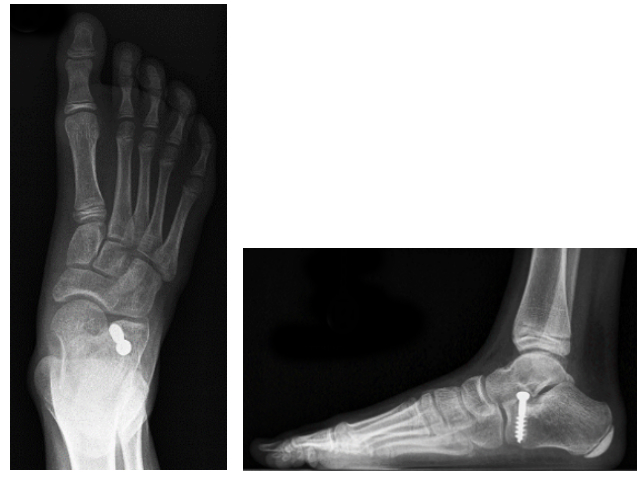

Juli's Fuss-OP

Oktober 2018, der Knochen muss gerichtet werden.